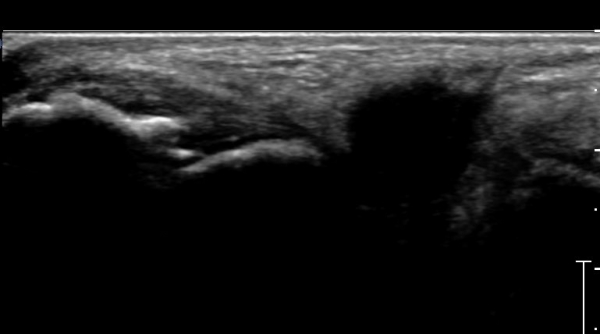

Á¾°ñºñ°ñÀδë Á¾´Ü¸é°Ë»ç¿¡¼­ °Å°ñÇϰüÀýÀÇ ¼ö¾×Àú·ù(Á¾°ñºñ°ñÀÎ´ë ½ÉºÎ ¼ö¾×Àú·ù)°¡

°üÂûµÈ´Ù(»çÁø 4).